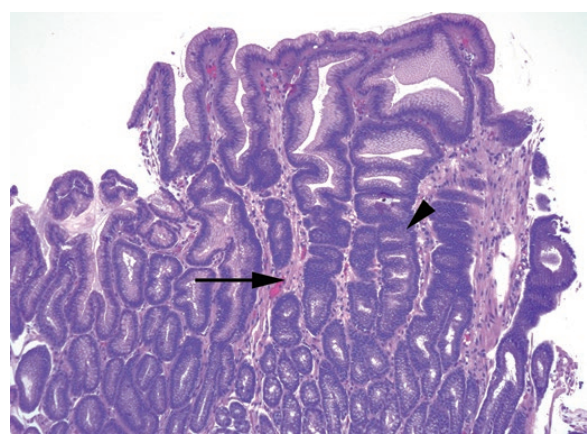

Goblet cells in Barrett’s esophagus. The presence of columnar epithelium with goblet cells indicates Barrett’s esophagus. Goblet cells are round cells that appear clear on H&E stain and are typically flanked by the purplish absorptive-type cells. Back-to-back mucinous cells resembling a row of teeth are more likely to be gastric foveolar epithelium. Goblet cells may be present at the surface (arrow) or in deep glands (arrowhead). Inset: A PAS/AB stain confirms the goblet cells, which stain indigo blue (arrowhead).